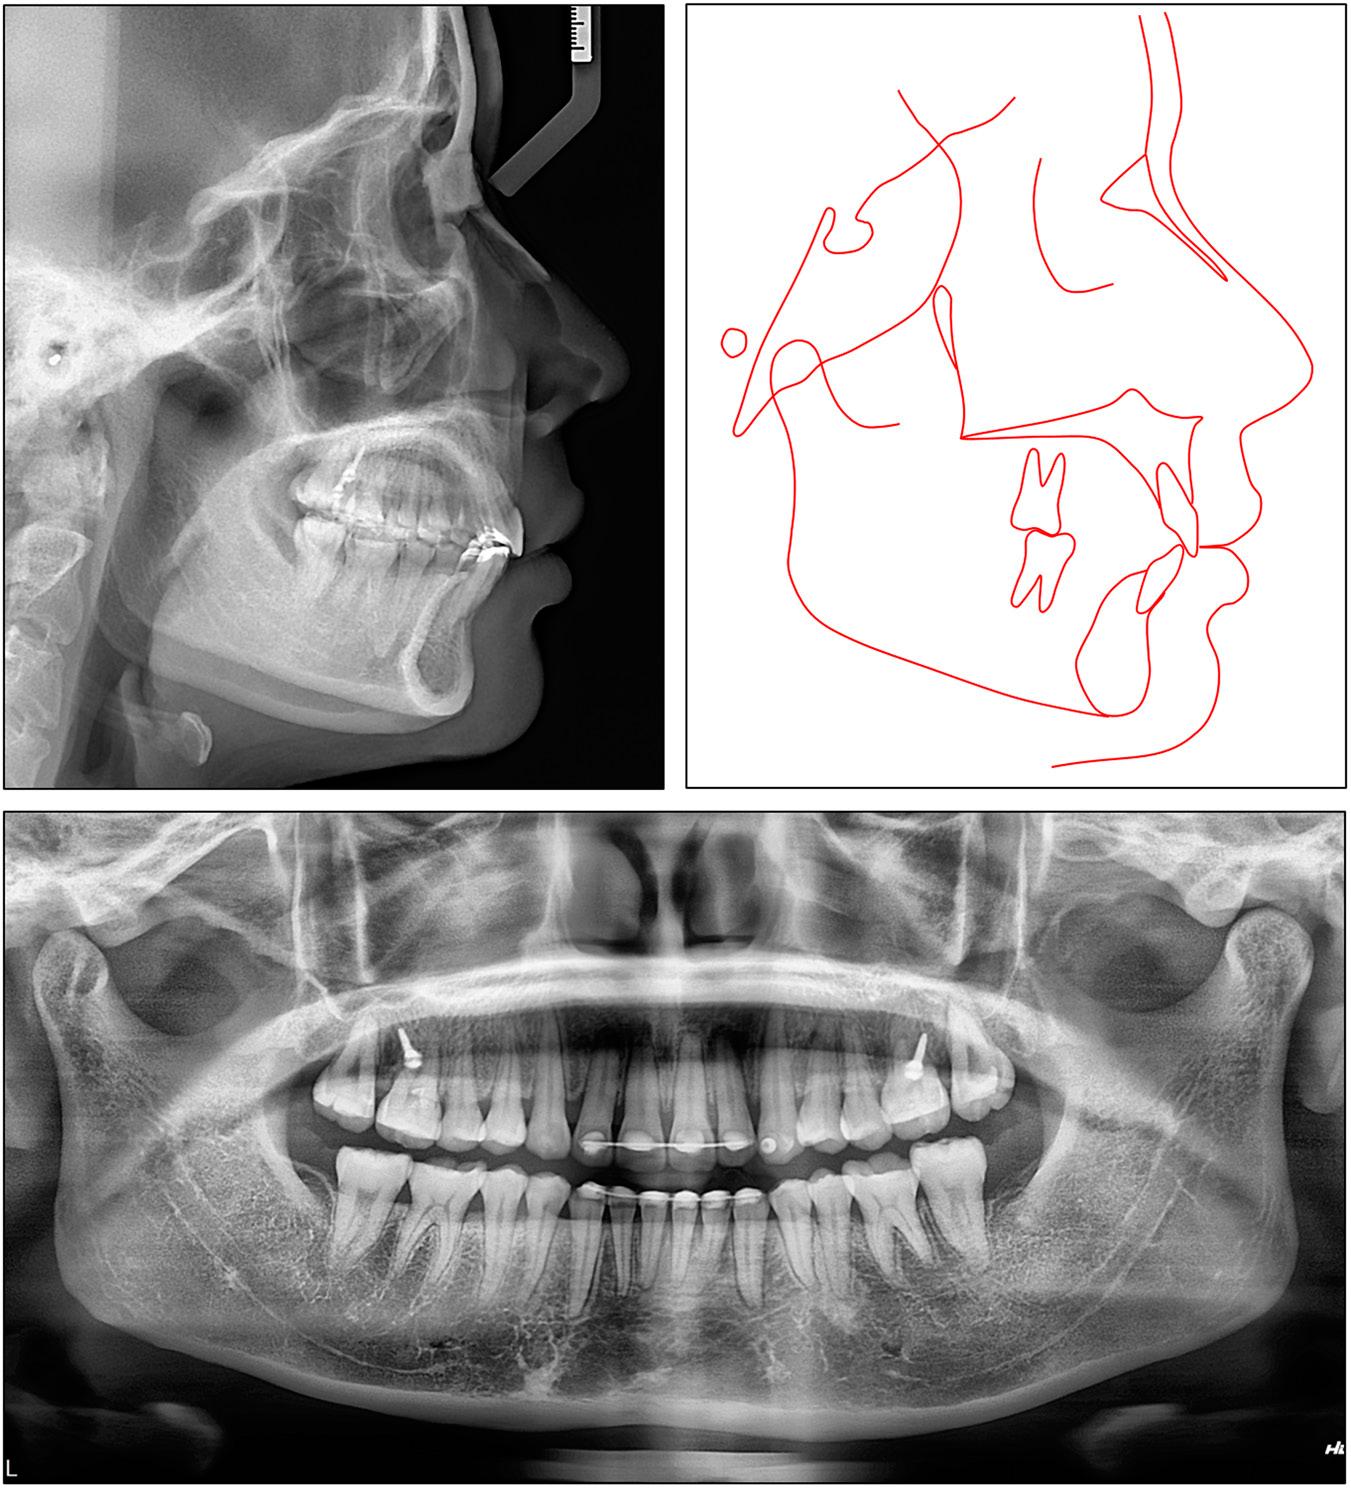

Cephalometric measurements of case 2

| Pretreatment | Posttreatment | |

|---|---|---|

| Skeletal | ||

| SNA (°) | 85.5 | 83.0 |

| SNB (°) | 75.8 | 75.0 |

| ANB (°) | 9.7 | 8.0 |

| FMA (°) | 21.4 | 22.1 |

| Dental | ||

| U1-SN (°) | 73.9 | 94.1 |

| U1-PP (°) | 83.1 | 104.3 |

| U1-NA (°) | -11.7 | 11.1 |

| U1-NA (mm) | -5.7 | -2.2 |

| IMPA (°) | 103.4 | 106.0 |

| L1-NB (°) | 29.4 | 33.0 |

| L1-NB (mm) | 5.3 | 6.8 |

| Interincisal angle (°) | 152.5 | 127.9 |

| Upper incisal display (mm) | 3.7 | 2.3 |

| Soft tissue | ||

| E-line/UL (mm) | 1.9 | -1.5 |

| E-line/LL (mm) | 0.2 | -0.9 |